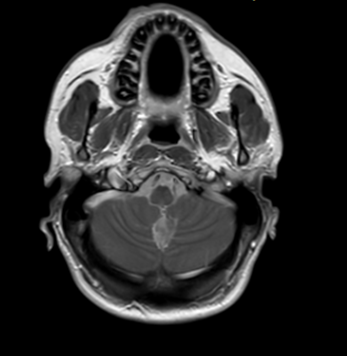

Se toman imágenes de control observando progresión de processo inflamatório a nível cerebral y a nível lumbar (figuras 4 y 5), progresión de siringomielia com afectación a nível cervical (figura 6)

Realce leptomeníngeo. Afectación de cisternas de la base

Figura 6